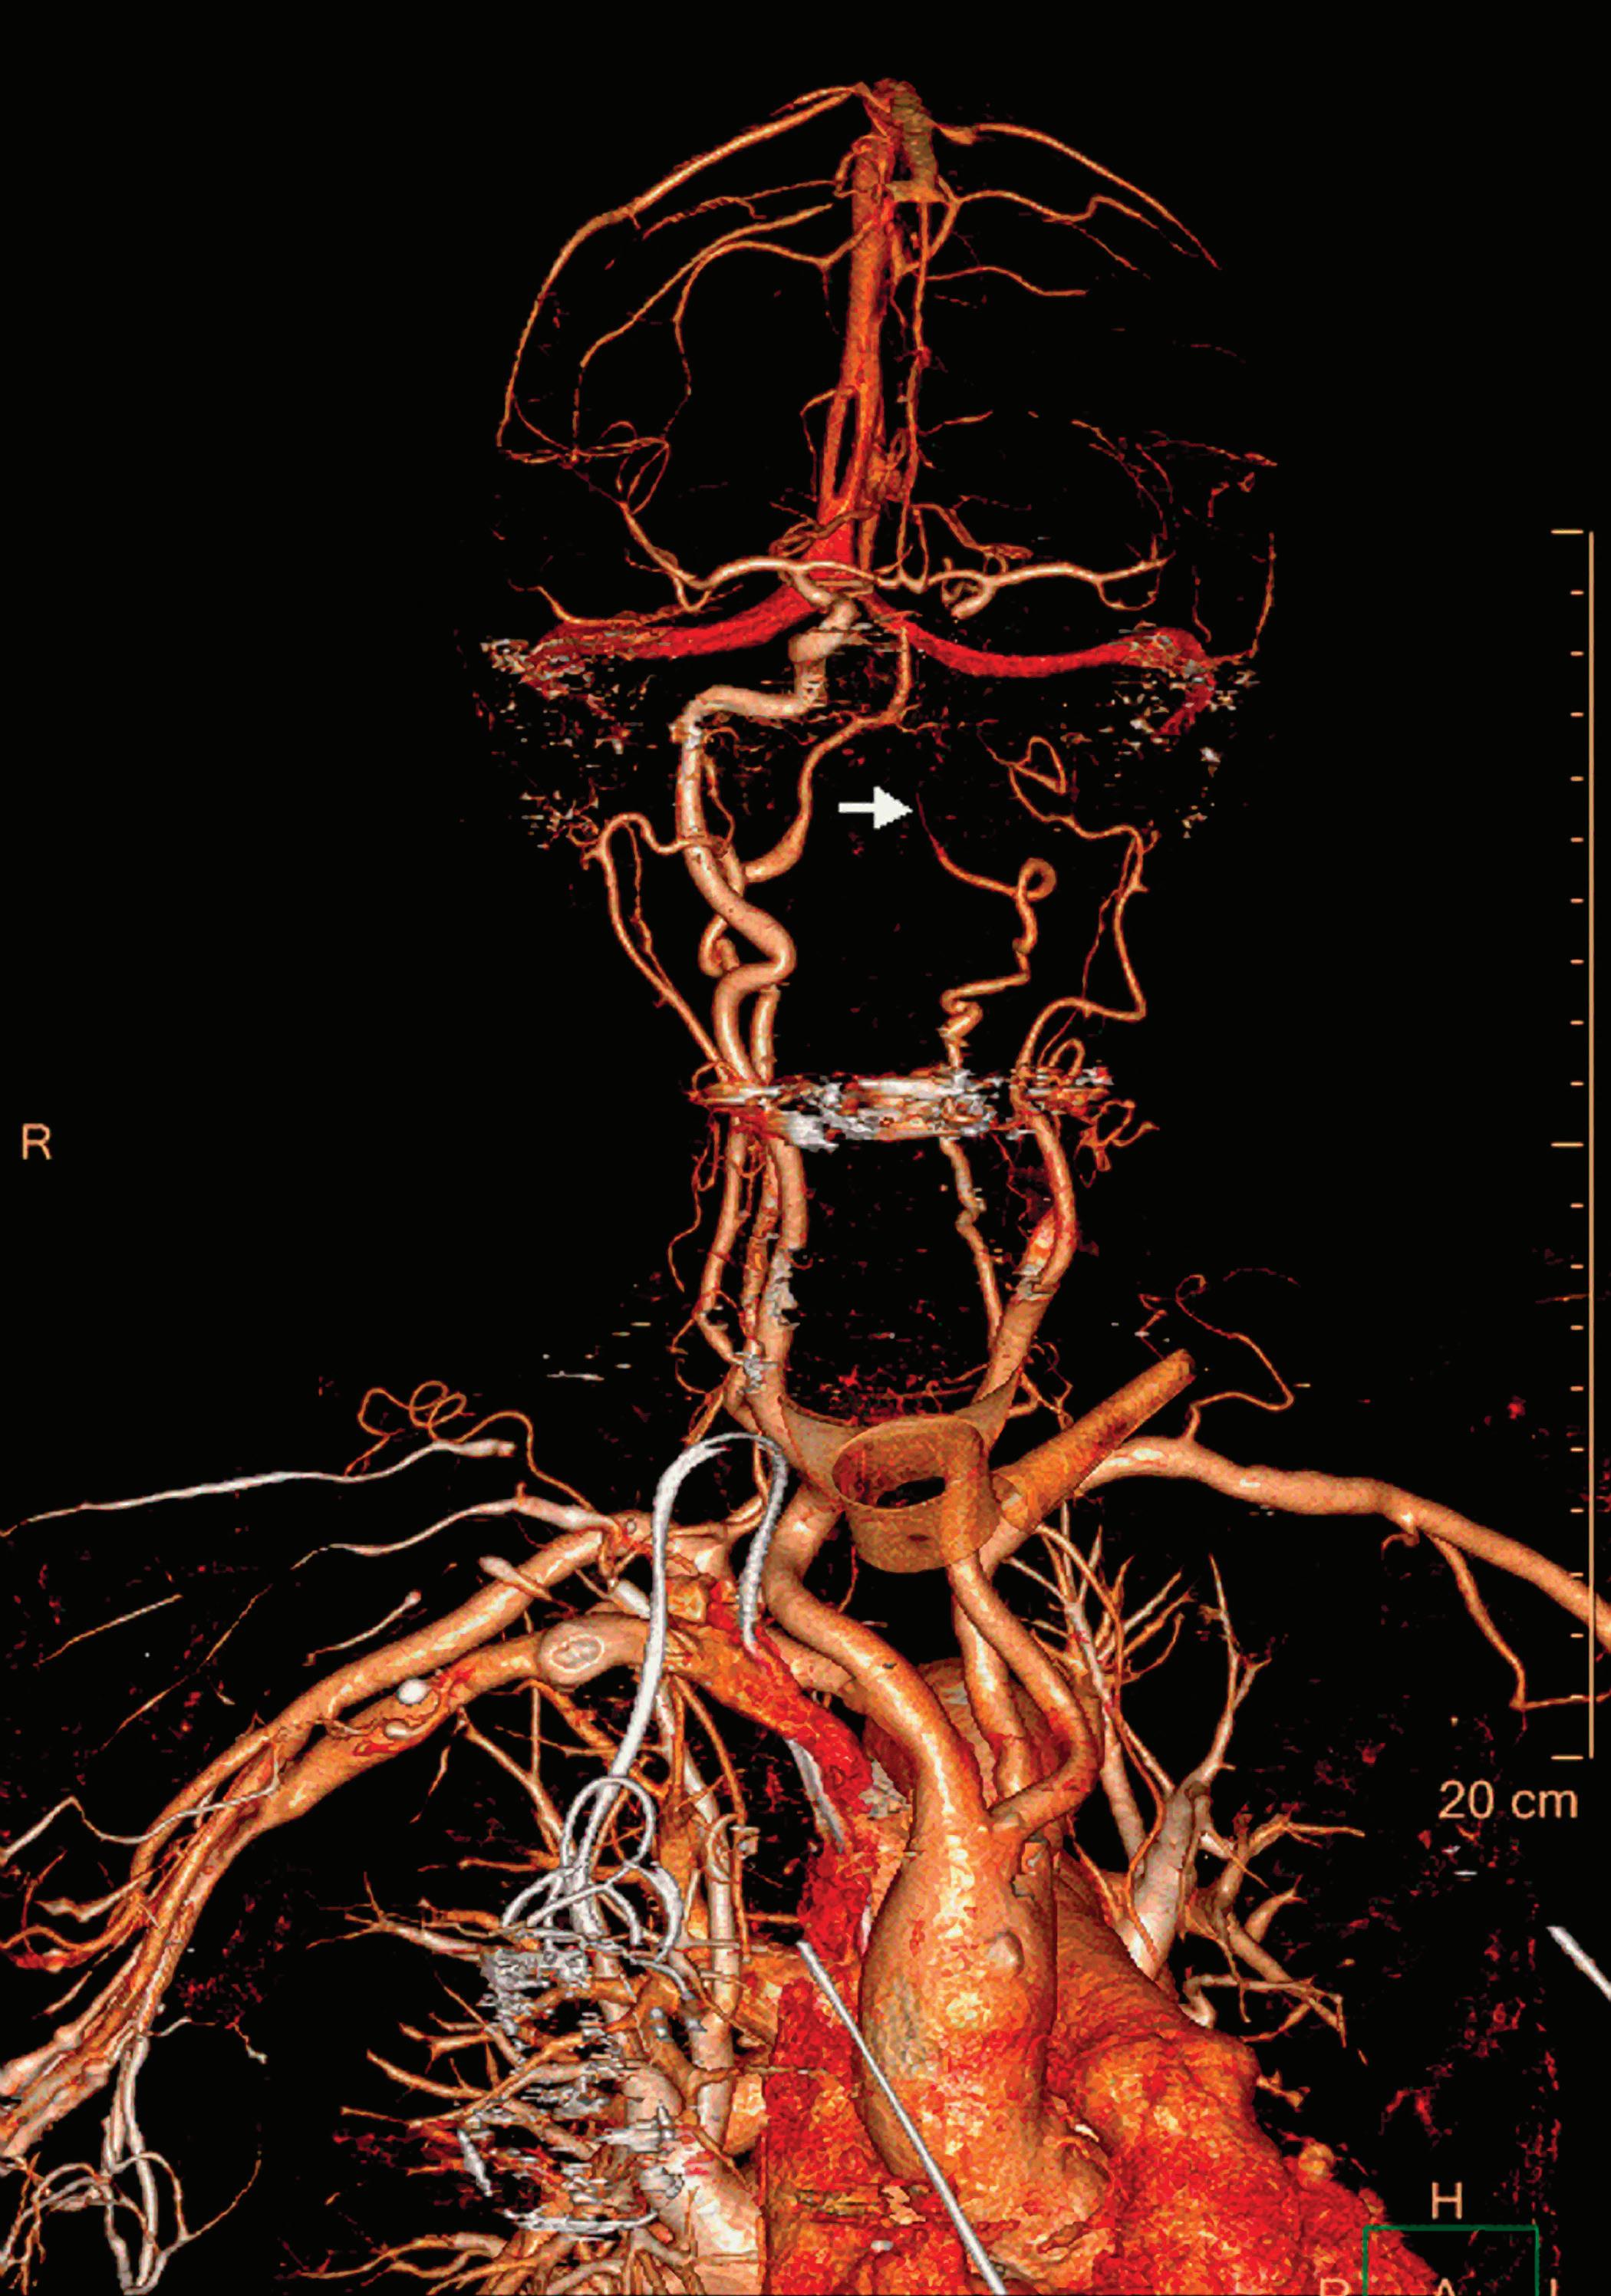

Contrast enhanced structures displayed in volume rendering (VR) obtained from the axial monoenergetic 70 keV images where only the voxels classified as not bone are shown and others appear black. White arrow points to a narrowed left basilar artery.

Contrast-Enhanced Structures [HU]

Voxels that are not classified as bone show the corresponding HU of the reference monoenergetic 70 keV CT image. Other voxels appear black (Figure 5). These structures can, for example, be used as color overlays placed above other spectral results to enhance the regions with contrast uptake.